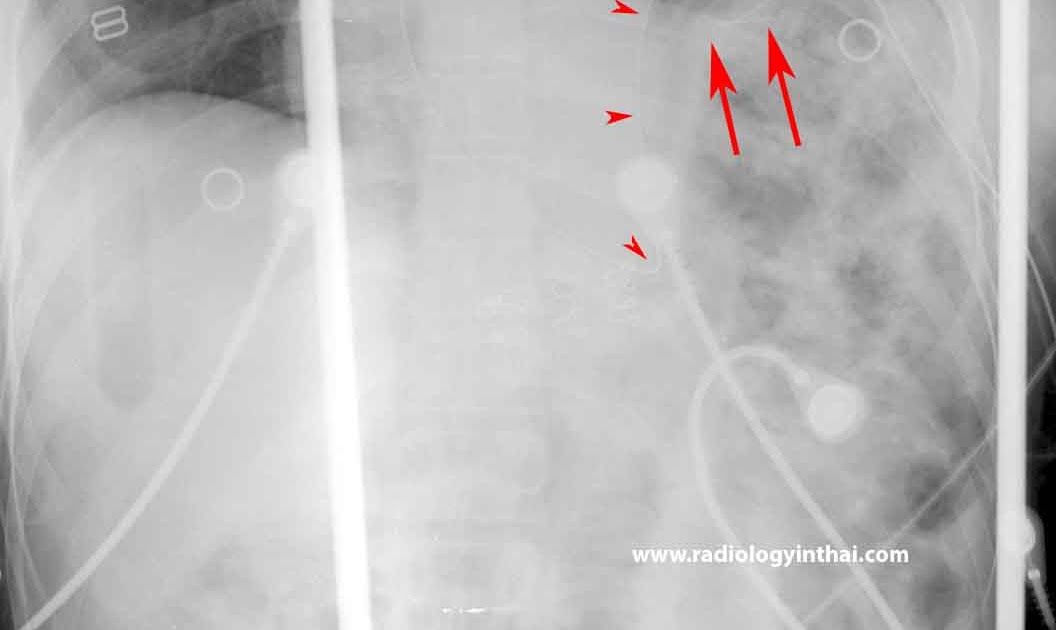

RiT radiology Blunt Diaphragmatic Rupture What Does A Damaged Diaphragm Feel Like Traumatic injury to the diaphragm is rare. what happens if the diaphragm is damaged? some people also experience sweating and anxiety during a diaphragm spasm. if you love working out, you may experience a tight diaphragm. When this happens, you feel a sharp pain on your. the most common conditions include hernias and nerve damage from. What Does A Damaged Diaphragm Feel Like.